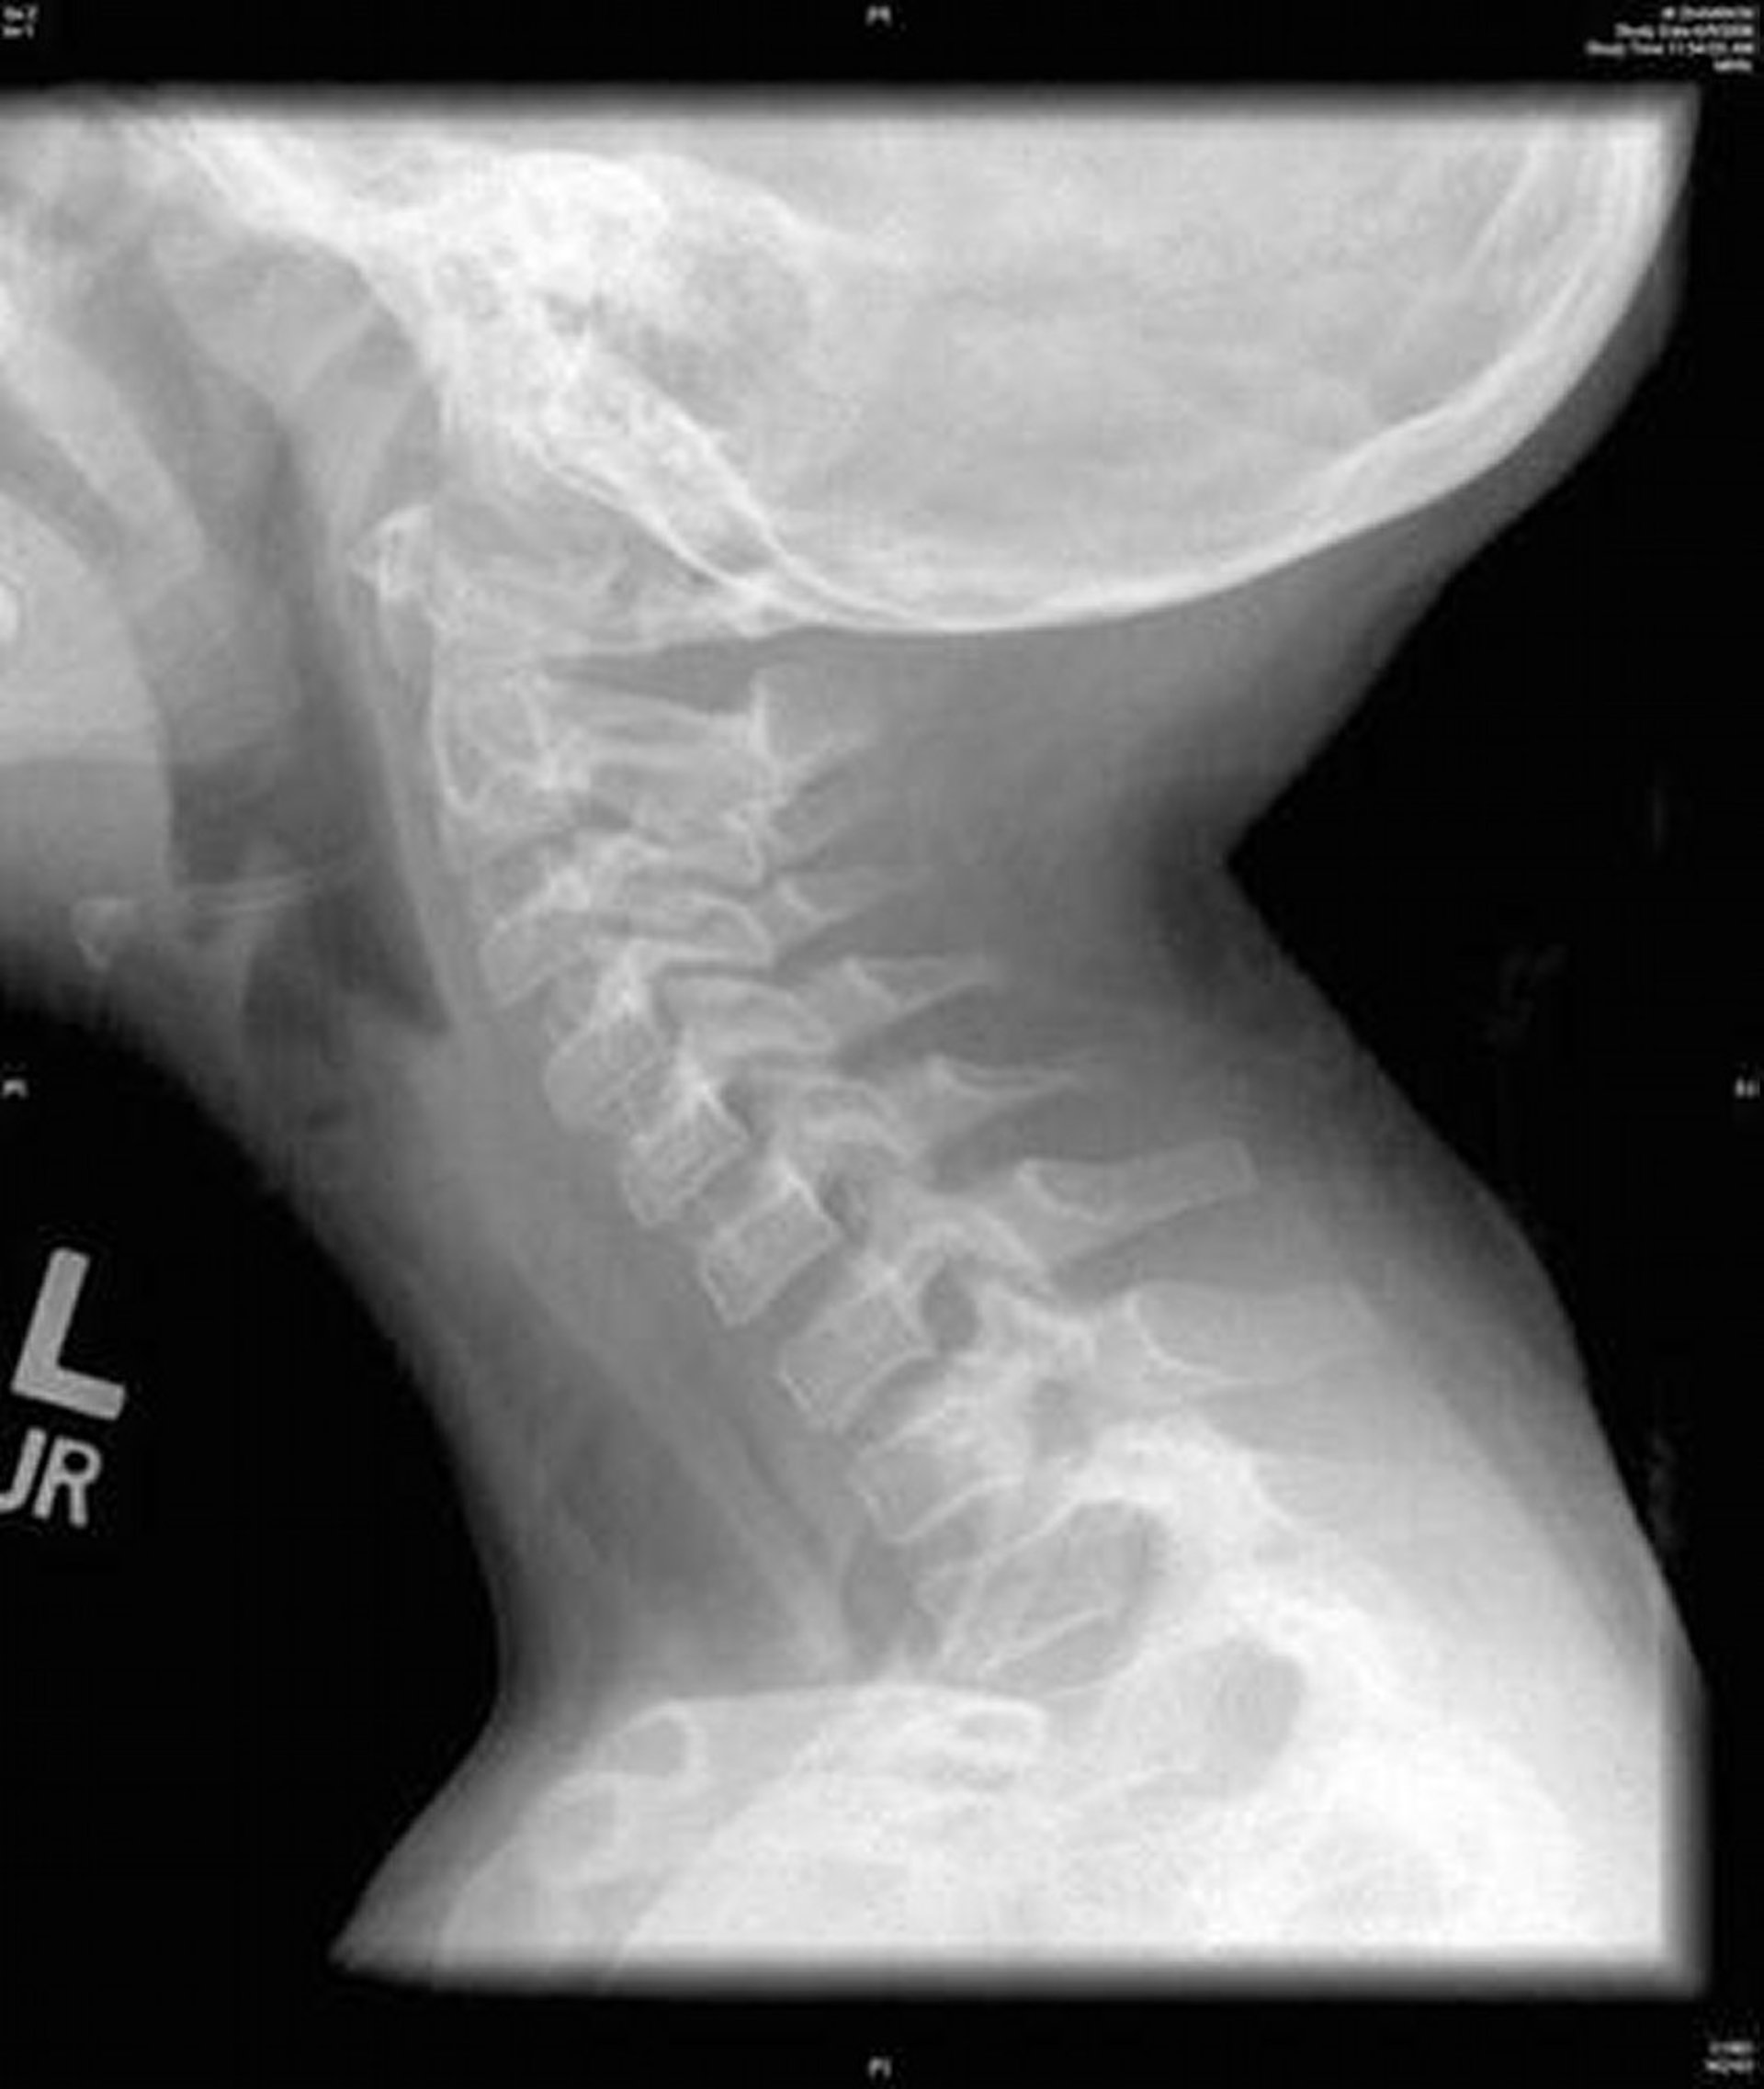

細菌性気管炎(X線)

この画像は,細菌性気管炎の特徴である気管の広範な不整を認める頸部のX線側面像を示している。